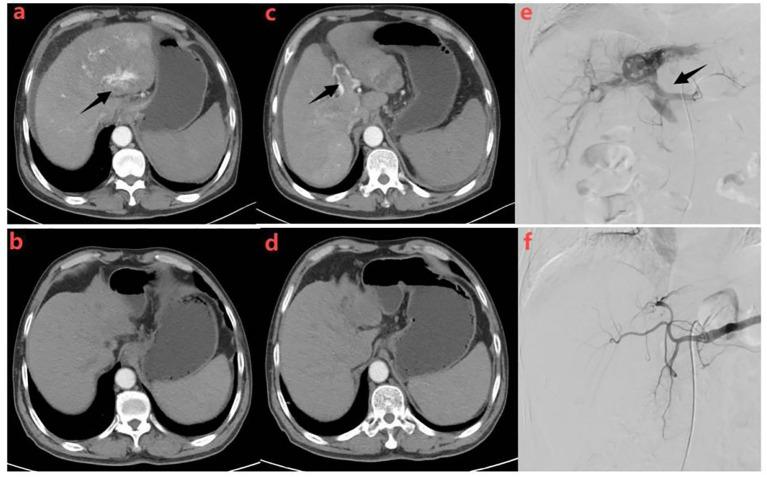

Triple therapy revolutionizes treatment paradigms for previously untreatable HCC complicated by high-flow hepatic arteriovenous fistulas.

To evaluate the short-term efficacy and safety of hepatic arterial infusion chemotherapy (HAIC) combined with immune checkpoint inhibitors (ICIs) and tyrosine kinase inhibitors (TKIs) in patients with hepatocellular carcinoma (HCC) complicated by high-flow hepatic arteriovenous fistula (HAVF).

We retrospectively analyzed clinical data from 40 patients with unresectable HCC complicated by high-flow HAVF who received FOLFOX regimen HAIC plus ICIs and TKIs between January 2021 and June 2023. The efficacy evaluation included HAVF effective rate, tumor response, progression-free survival (PFS), overall survival (OS) per RECIST 1.1 and mRECIST. Adverse events (AEs) were recorded for safety evaluation.

The median follow-up time was 10.5 months (range: 3.5-16.4 months). A total of 150 HAIC cycles were administered, with a median frequency of 3.8 cycles per patient. The objective response rate (ORR) and the disease control rate (DCR) was 42.5% and 92.5% according to the RECIST 1.1, and 75.0% and 92.5% according to mRECIST criteria, respectively. The median PFS and the median OS were 5.5 months (95% CI: 3.9-6.9) and 10.4 months (95% CI: 7.4-13.4), respectively. In univariate analysis, HAVF grade, extrahepatic spread, HAVF disappearance were potential prognostic factors for OS, while HAVF grade and extrahepatic spread being independently associated with PFS. Hypertension (12.5%), Thrombocytopenia (12.5%) and Albumin decreased (7.5%) were the most frequently observed grade 3-4 TRAEs.No treatment-related mortality occurred during the study period.

HAIC combined with ICIs and TKIs demonstrates promising short-term efficacy and acceptable safety in patients with unresectable HCC complicated by high-flow HAVF. This combination therapy effectively controls tumor growth while simultaneously managing the arteriovenous shunt, providing a valuable treatment option for this challenging patient population.